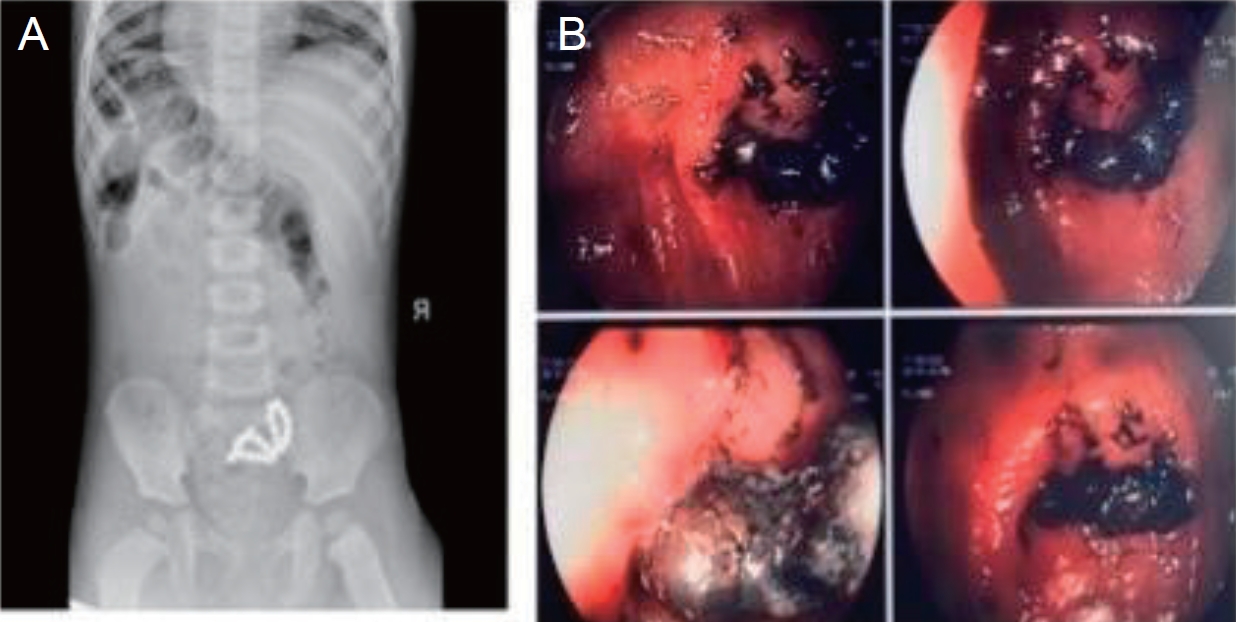

Fig. 2.

(A) Radiograph showing ingested magnets. (B) Endoscopic findings of ingested magnets forming a fistula between intestinal folds.

5) Magnets (Figs. 1E and 2)

8. Magnets

Magnet swallowing (Fig. 2) is a serious and sometimes life-threatening problem requiring that requires special management. Swallowing one or more high-powered magnets, especially if swallowed at different times, can trap the mucosa, through an attractive force between them, resulting in pressure, necrosis, perforation, inflammation, obstruction and further complications such as bowel resection. Magnet ingestion requires immediate evaluation using, cervical, thoracic, abdominal, and lateral radiographs. Mucosal entrapment cannot always be assessed using radiography; however, the consistent presence of slightly separated magnets is indicative of this issue. Even when a single high-power magnet is swallowed, there is a risk of mucosal entrapment may occur due to internal or external contact with another metal object on the individual's clothing, jewelry, or belts. Repeated radiographs are then used to determine whether are multiple magnets which may mistakenly suggest that they are one (fused together). Thus, immediate removal from the esophagus, stomach, or proximal duodenum is recommended if multiple magnets or other metallic objects have been swallowed. I case the magnets have advanced into the intestine, asymptomatic patients should undergo close clinical monitoring and radiographs every 4–6 hours. Alternatively, an attempt should be made to remove them using enteroscopy or colonoscopy if feasible. If patients are symptomatic, immediate surgical resection is recommended.